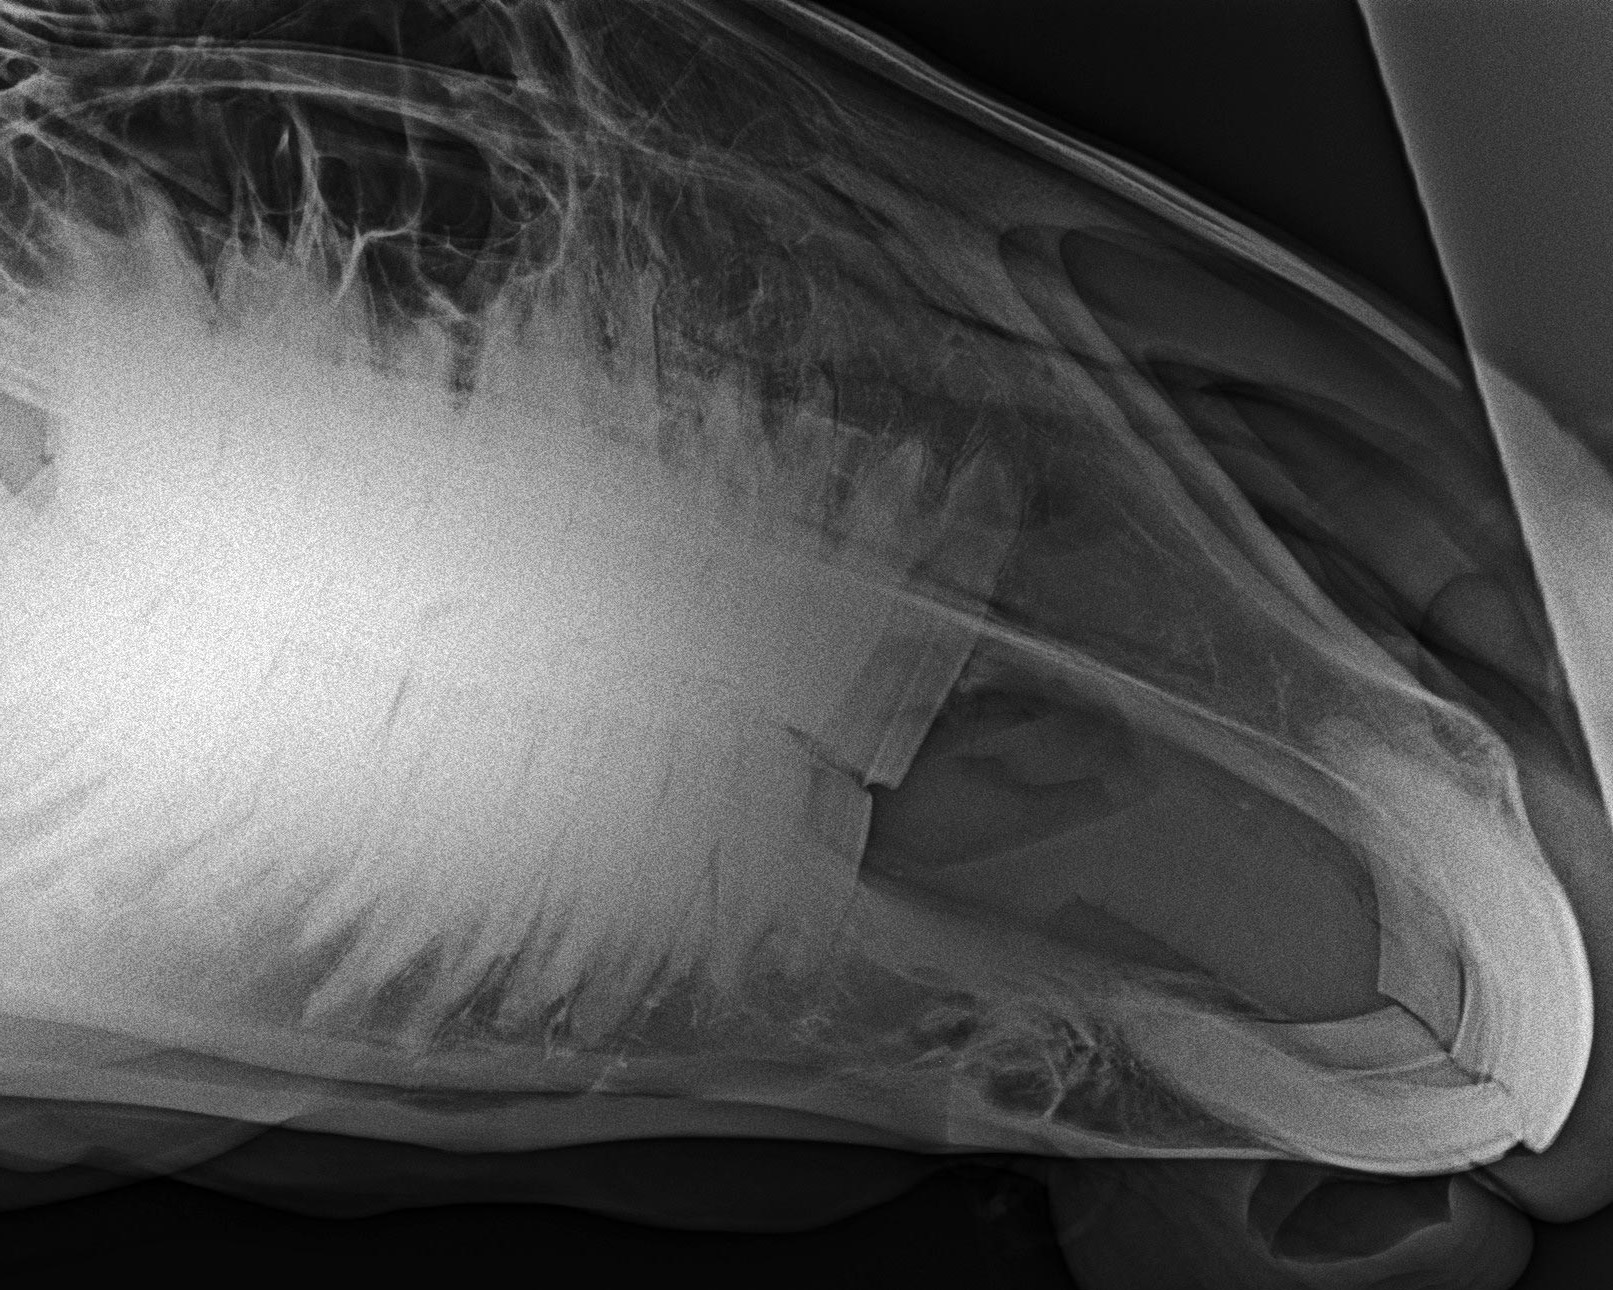

Kopfaufnahme